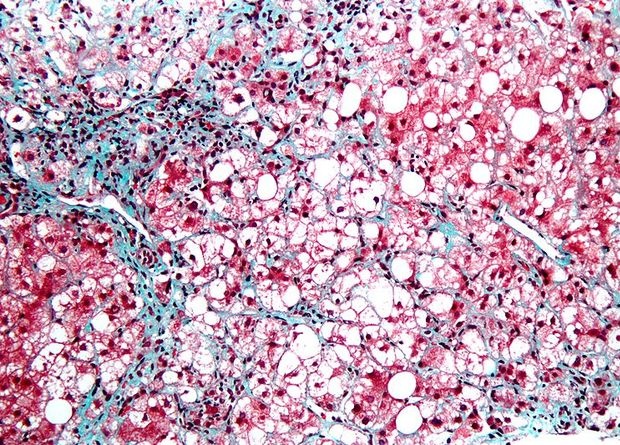

Сенесцентные клетки, которые накапливаются в тканях при старении, во многом напоминают опухолевые. Они точно так же не выполняют своих основных функций в ткани, но вместо этого запускают перестройку межклеточного вещества, и в них точно так же заблокированы механизмы клеточного самоубийства — апоптоза.

Поэтому в качестве сенолитиков — препаратов, которые призваны очистить ткань от старых клеток — тестируют некоторые противоопухолевые лекарства, так как они действуют избирательно на клетки с заблокированным апоптозом. В отдельных экспериментах сенолитики уже показали свою способность продлевать жизнь мышам и улучшать (правда, пока незначительно) состояние людей с разными возрастными заболеваниями, например, воспалением суставом, фиброзом легких и диабетом.